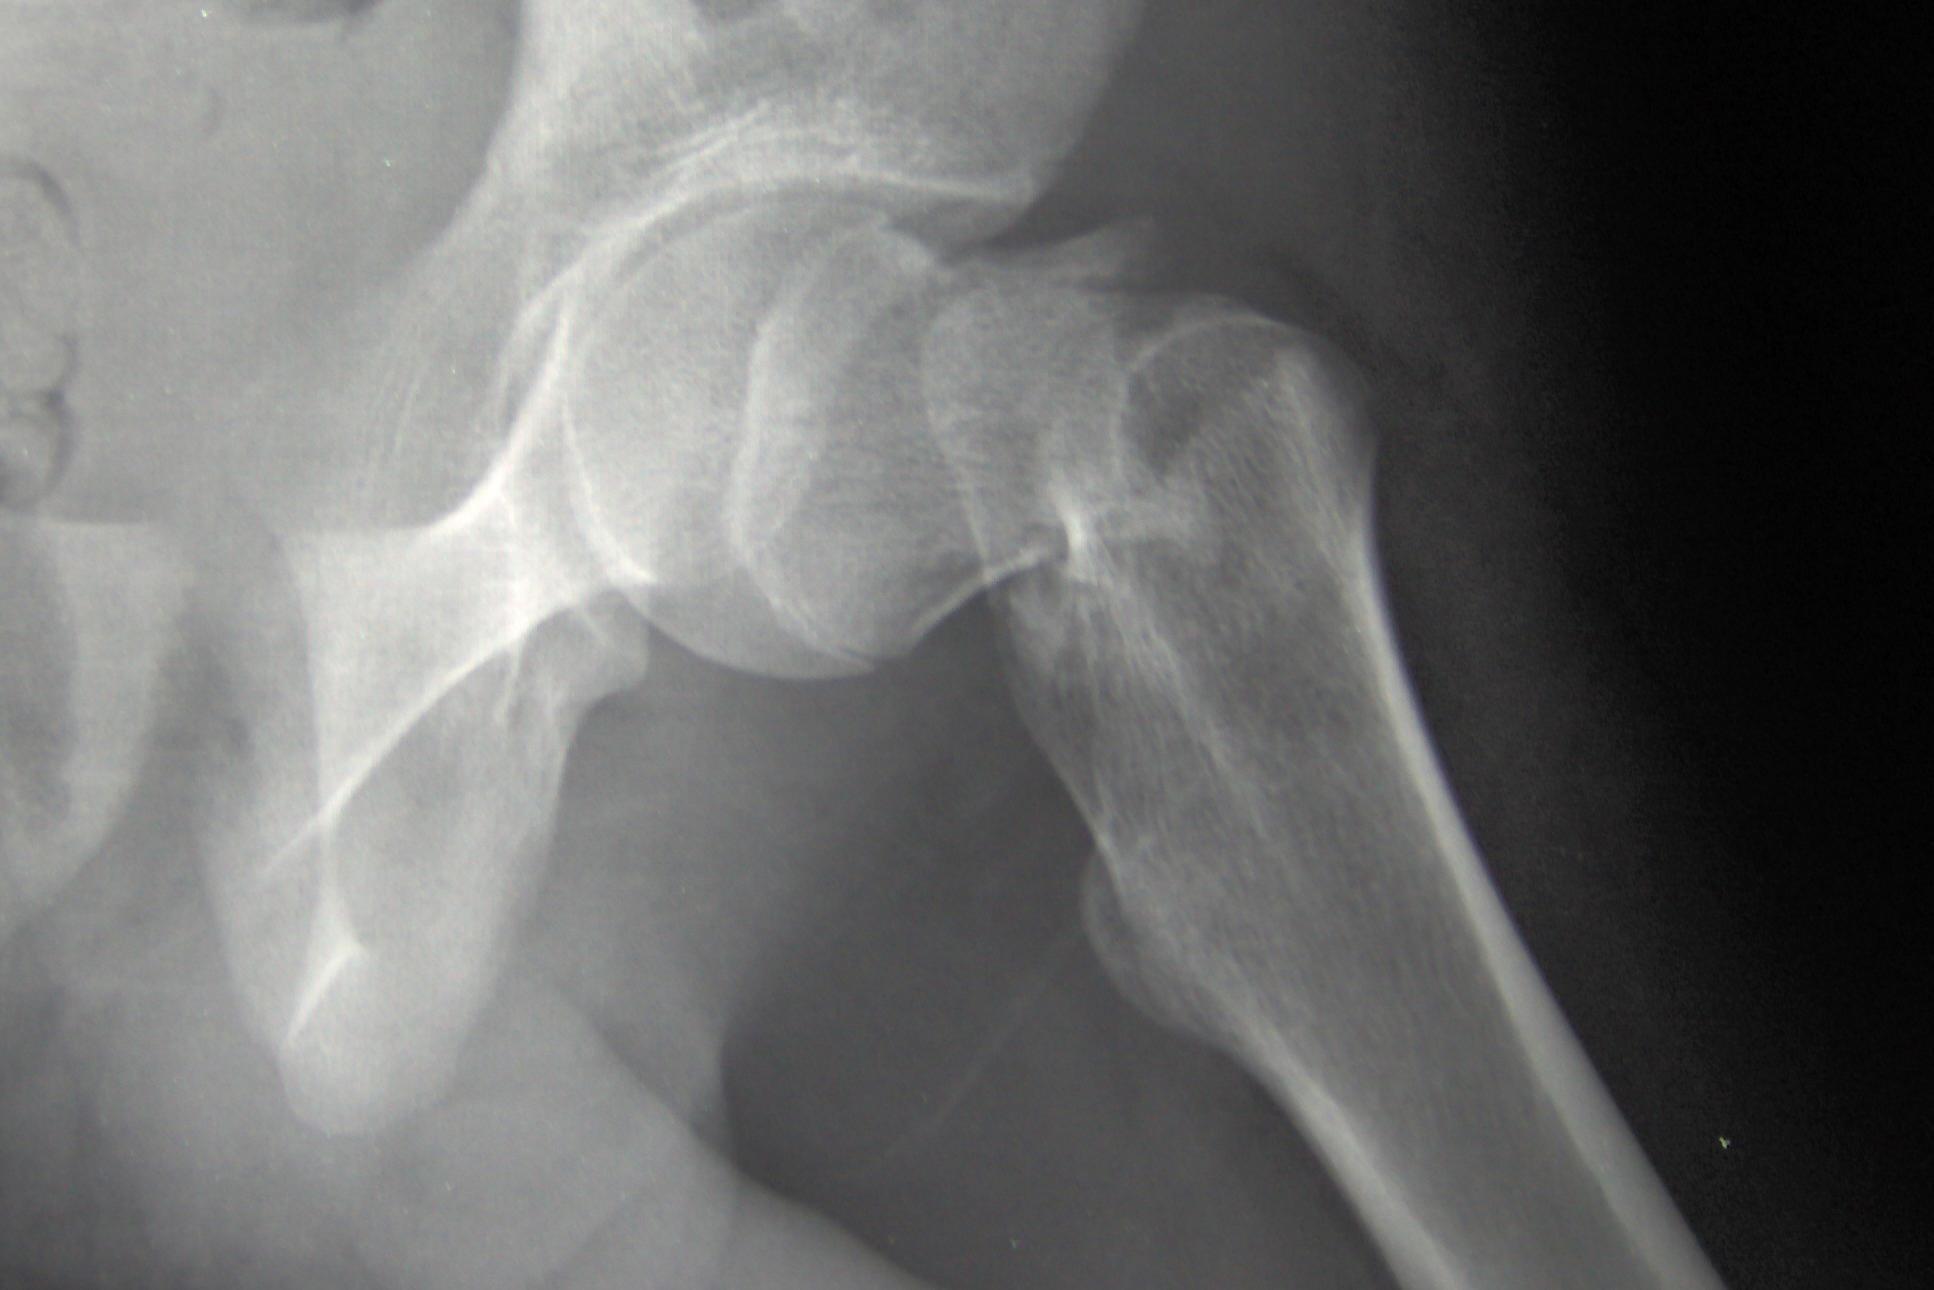

When it comes to the mechanism of calcium, based on animal studies Dr. Weaver has conducted, there is no reason for concern, but the differing schools of thought in academia is pushing consumers to think if they are risking cardiovascular health for osteoporosis, or vice versa?

“If we get children and adolescents to build the strongest, healthiest bones, then we could offset the osteoporosis or maybe even completely prevent it later in life, and one of the determinants was calcium intake,” he said about a new position paper he helped author with the NOF, published in the journal Osteoporosis International. “You can definitely see in children that increased calcium consumption means larger, stronger bones.”